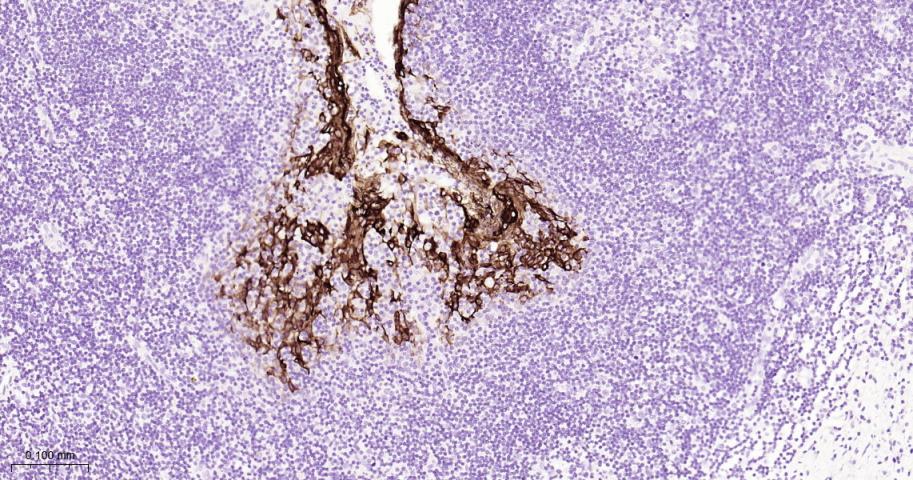

Paraformaldehyde-fixed, paraffin embedded Human Esophagus; Antigen retrieval by boiling in sodium citrate buffer (pH6.0) for 15 min; The section was incubated with Cytokeratin 6 Monoclonal Antibody, Unconjugated (bsm-63151R) at 1:200 overnight at 4°C, followed by conjugation to the bs-0295G-HRP and DAB (C-0010) staining.

Paraformaldehyde-fixed, paraffin embedded Human Cervical Cancer; Antigen retrieval by boiling in sodium citrate buffer (pH6.0) for 15 min; The section was incubated with Cytokeratin 6 Monoclonal Antibody, Unconjugated (bsm-63151R) at 1:200 overnight at 4°C, followed by conjugation to the bs-0295G-HRP and DAB (C-0010) staining.

Paraformaldehyde-fixed, paraffin embedded Human lung squamous cell carcinoma; Antigen retrieval by boiling in sodium citrate buffer (pH6.0) for 15 min; The section was incubated with Cytokeratin 6 Monoclonal Antibody, Unconjugated (bsm-63151R) at 1:200 overnight at 4°C, followed by conjugation to the bs-0295G-HRP and DAB (C-0010) staining.

Paraformaldehyde-fixed, paraffin embedded Human Tonsil; Antigen retrieval by boiling in sodium citrate buffer (pH6.0) for 15 min; Antibody incubation with Cytokeratin 6 Monoclonal Antibody, Unconjugated(bsm-63151R) at 1:200 overnight at 4°C, followed by conjugation to the bs-0295G-HRP and DAB (C-0010) staining.

Paraformaldehyde-fixed, paraffin embedded Human Abdominal skin; Antigen retrieval by boiling in sodium citrate buffer (pH6.0) for 15 min; The section was incubated with Cytokeratin 6 Monoclonal Antibody, Unconjugated (bsm-63151R) at 1:200 overnight at 4°C, followed by conjugation to the bs-0295G-HRP and DAB (C-0010) staining.